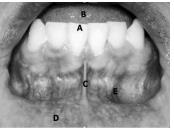

Considerando a fotografia intrabucal apresentada acima, julgue a pertinência da correlação da área indicada na figura com a respectiva descrição.

A: borda incisal de um dente incisivo central inferior.